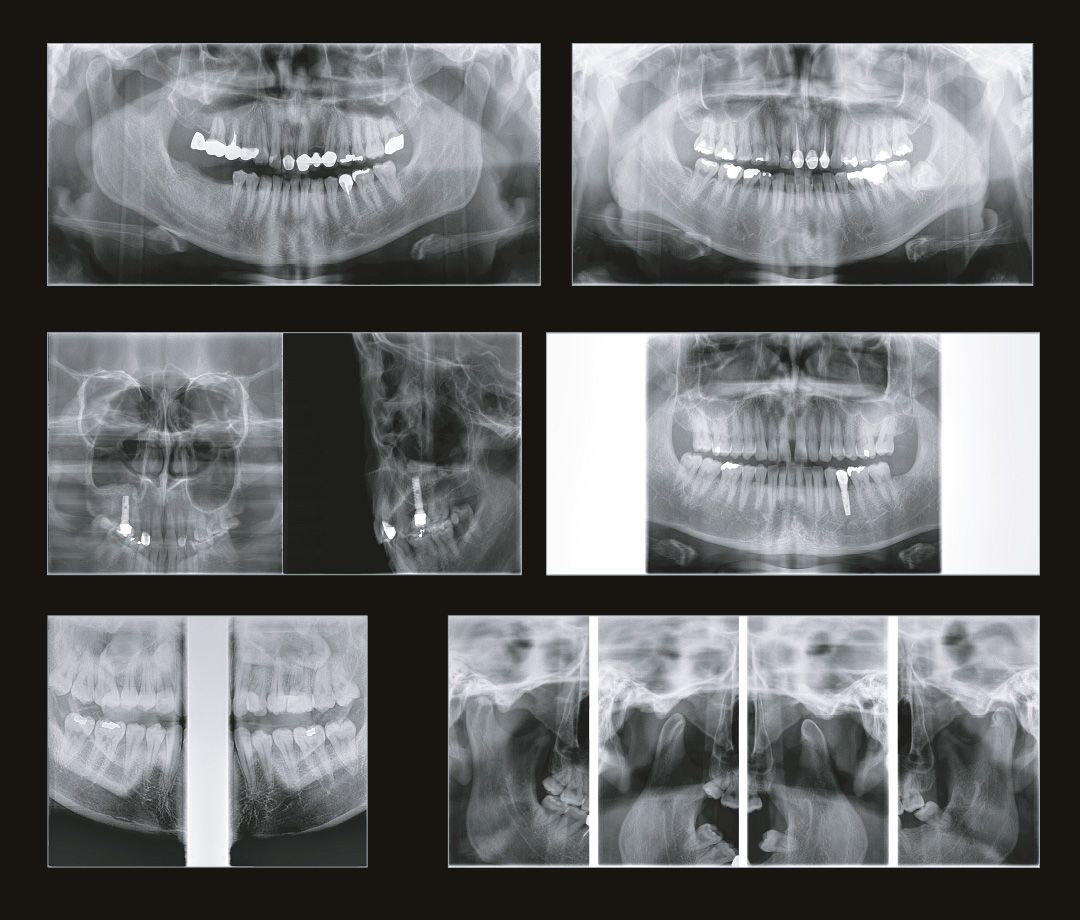

Алгоритм уменьшения вторичного излучения от металлов

Умная Функция Уменьшения Артефактов от Металла (Smart Metal Artifact Reduction Function) – позволяет минимизировать артефакты от вторичного излучения металлов и получить необходимую диагностическую информацию для постановки корректного диагноза, а также планирования и контроля проведенного лечения.

SMARF - алгоритм уменьшения вторичного улучшения от металлов дентального компьютерного 3D томографа.jpg